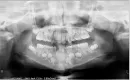

Дочке 7 лет. Центральные нижние резцы выросли как-то сбоку. Получается, что на месте трех резцов только два. Расти некуда, ортодонт рекомендует вырвать молочный клык, чтобы освободить место для не помещающегося резца. Раздвинуть, сказал, никак не получится, только брекеты не раньше 12 лет.

Снимка недостаточно для составления плана лечения, необходим очный осмотр, оценка прикуса и состояние зубов. Если действительно недостаточно места в зубном ряду для прорезывания постоянного зуба и ортодонтические пластины не являются показанием в данном случае, тогда удаляют, какой либо молочный зуб. Брекеты ставят с 12 лет, не ранее.